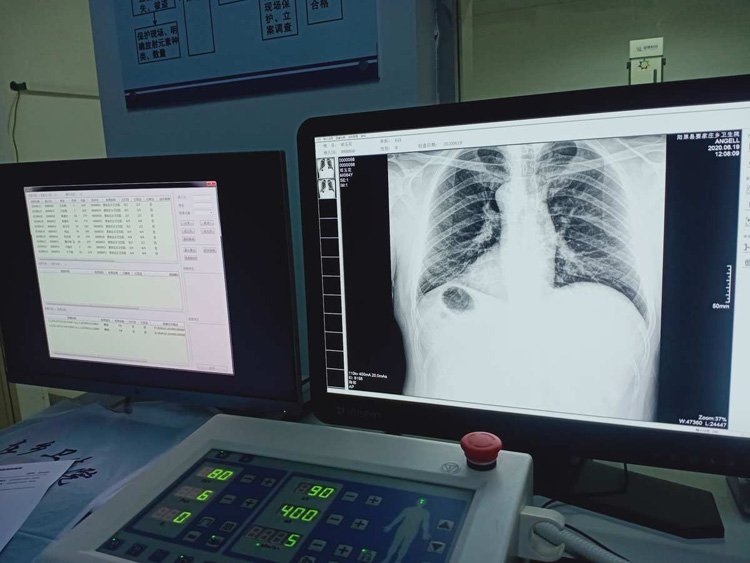

平床DR的平板探测器可以拍摄到高清的数字图像??梢约觳樯硖宓哪掣霾课?。头部、胸部、腹部、上肢、下肢、正位、侧位、都可以正常的拍摄。很小的剂量就可以采集到高清的检查图像。平板的稳定性也非常的强。DR的平板探测器跟图像结合。噪音低、图像的画质呈现丰富。图像的信息量会跟多提供给医生参考。帮助医生提高诊断的准确性。Digital Radiography就是数字化拍摄。平板探测器特性会对拍摄片的图片质量有关系。

平床DR的数字影像高分辨率,动态范围比较大,密度密度分辨率高可以看到更多细节。拍摄的速度快伪影小。比X光的的灵敏度高很多。辐射小的能量就可以拍到清晰的图像。辐射量少30%以上。特别是对骨头软组织的效果更优。对结节的有没病变的检测查出率更高。